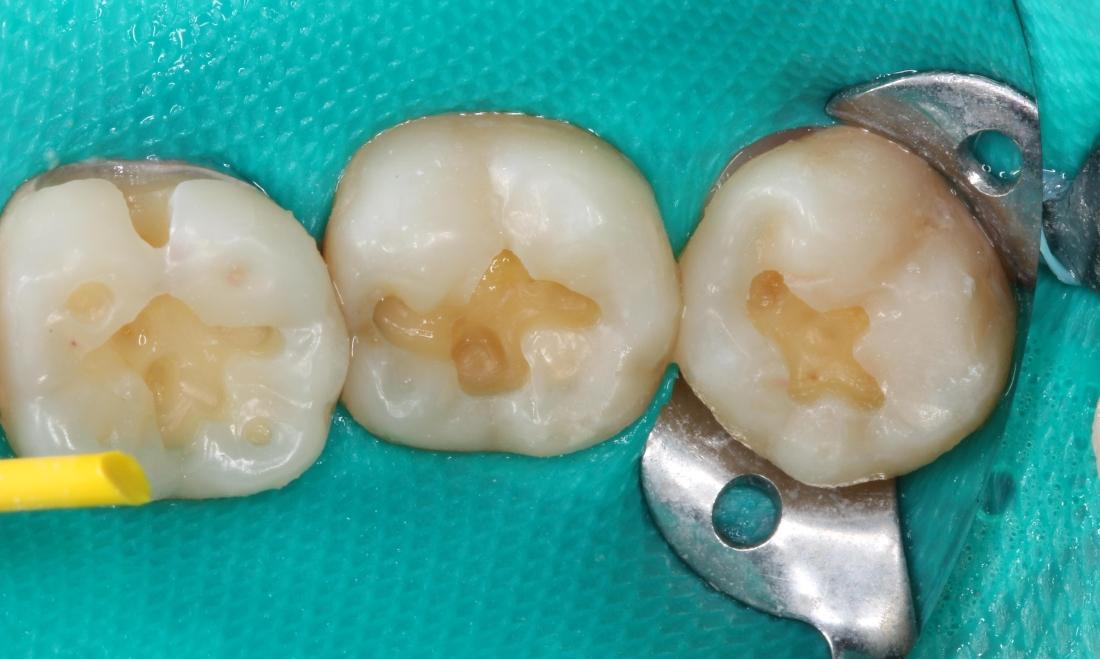

Our patient was having sensitivity on several teeth while eating and drinking sweet things. We found several large cavities in the pits and grooves of her molars. We used a green dental dam to isolate the teeth and prevent anything from contaminating the teeth. We then removed the cavities and rebuilt the teeth using white, tooth-colored composite filling material. We adjusted the bite after removing the dental dam and polished to make sure there were no rough areas. These fillings should last a long time with excellent home care and routine cleanings.